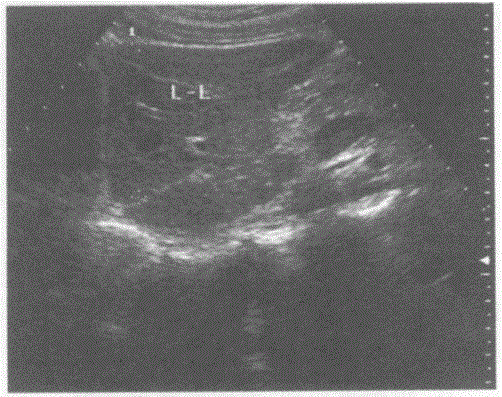

问题 请回答下图是采用哪种肝脏扫查方式:

选项 A.肝一胆囊纵切声像图 B.肝一下腔静脉纵切声像图 C.肝一胃纵切声像图 D.肝一尾状叶断面声像图

答案 D